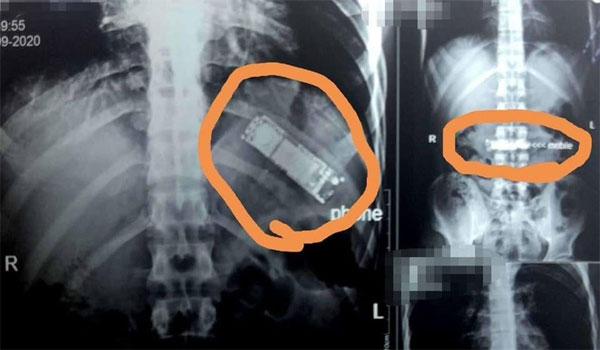

في حادثة غريبة، تمكن فريق طبي في مصر من استخراج هاتف محمول من معدة مواطن مصري كان قد ابتلعه منذ 7 أشهر.

ووصل المواطن حسن رشاد البالغ 28 عاماً إلى مستشفى بنها الجامعي، حيث كان يشكو من آلام بمعدته تعاوده من فترة لأخرى، وبفحصه وإجراء اللازم تبين وجود جسم غريب داخل بطنه.

كما أظهرت الفحوصات أن هذا الجسم الغريب هو هاتف جوال فيما قال المريض إنه ابتلعه خلال لحظة مزاح بينه وبين زملائه، لافتاً إلى أنه لم يبلغ أسرته بالواقعة ظناً منه أنه وبمجرد أن يقوم بالقيء في أي وقت سيتمكن من إخراج الهاتف من معدته.

وأجرى الفريق الطبي جراحة عاجلة للمريض استغرقت ساعتين واستخرج الهاتف من معدته.